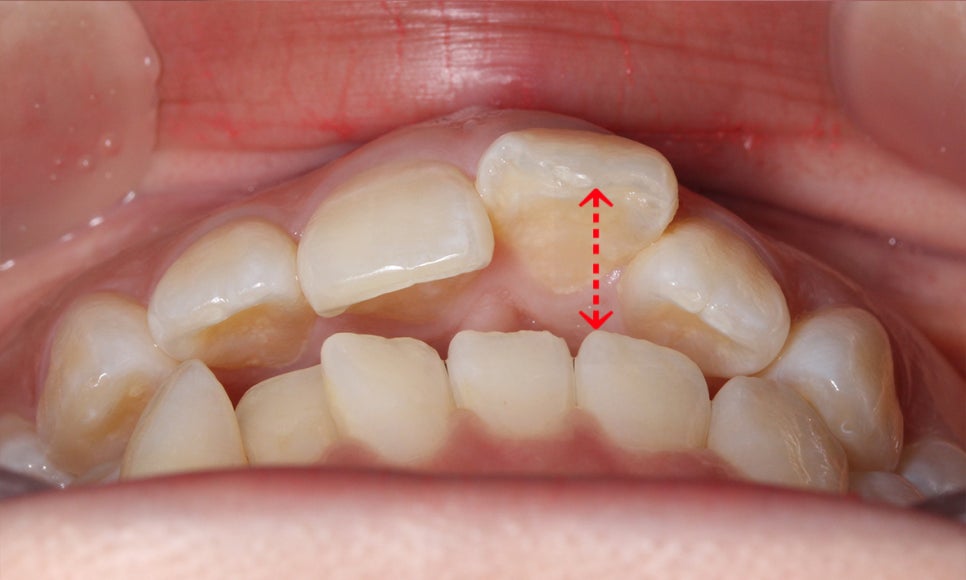

다음으로 상악과 하악의 교합면을 보시면

상악과 하악이 맞닿지 못하고 떨어져 있는 모습으로

구치부가 교합되고 있음에도 전치부 치열은 정확히

물리지 않는 모습인데요,

21번 치아가 순측으로 돌출되어 있기 때문에

앞니돌출 증상을 해결하고 전치부의 절단능력을

바르게 사용할 수 있도록 교정해야 합니다.

상악의 경우 교합면을 보시면

중절치의 뻐드러짐으로 인해

안모의 형태가 삐뚤어진 모습을 확인할 수 있습니다.